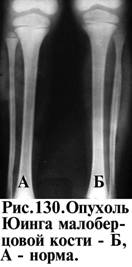

Локализация опухоли очень характерна. Некоторые опухоли имеют свою излюбленную локализацию, что может быть одним из диагностических симптомов. Так, хондромы локализуются в мелких костях кисти (рис. 127), гигантома (ОБК) у детей – в проксимальном метадиафизе плеча (рис. 128), а у взрослых – в проксимальном метаэпифизе большеберцовой кости. Остеогенная саркома локализуется в дистальном метафизе бедра (рис. 129), не нарушая зону роста и распространяется в диафиз. Саркома Юинга чаще поражает диафиз голени и предплечье.

· локализацию (рис. 130) очага (центральное или периферическое расположение);